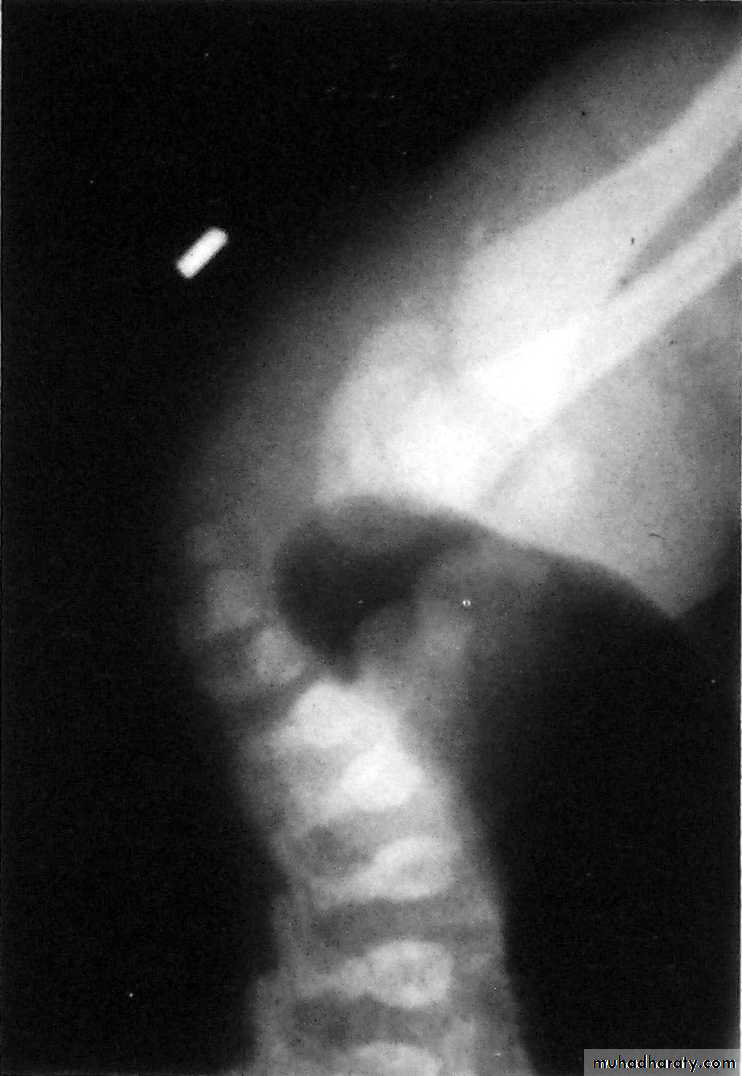

Slide 61- What we call this traction ?2 How much the weight which should be used with it?